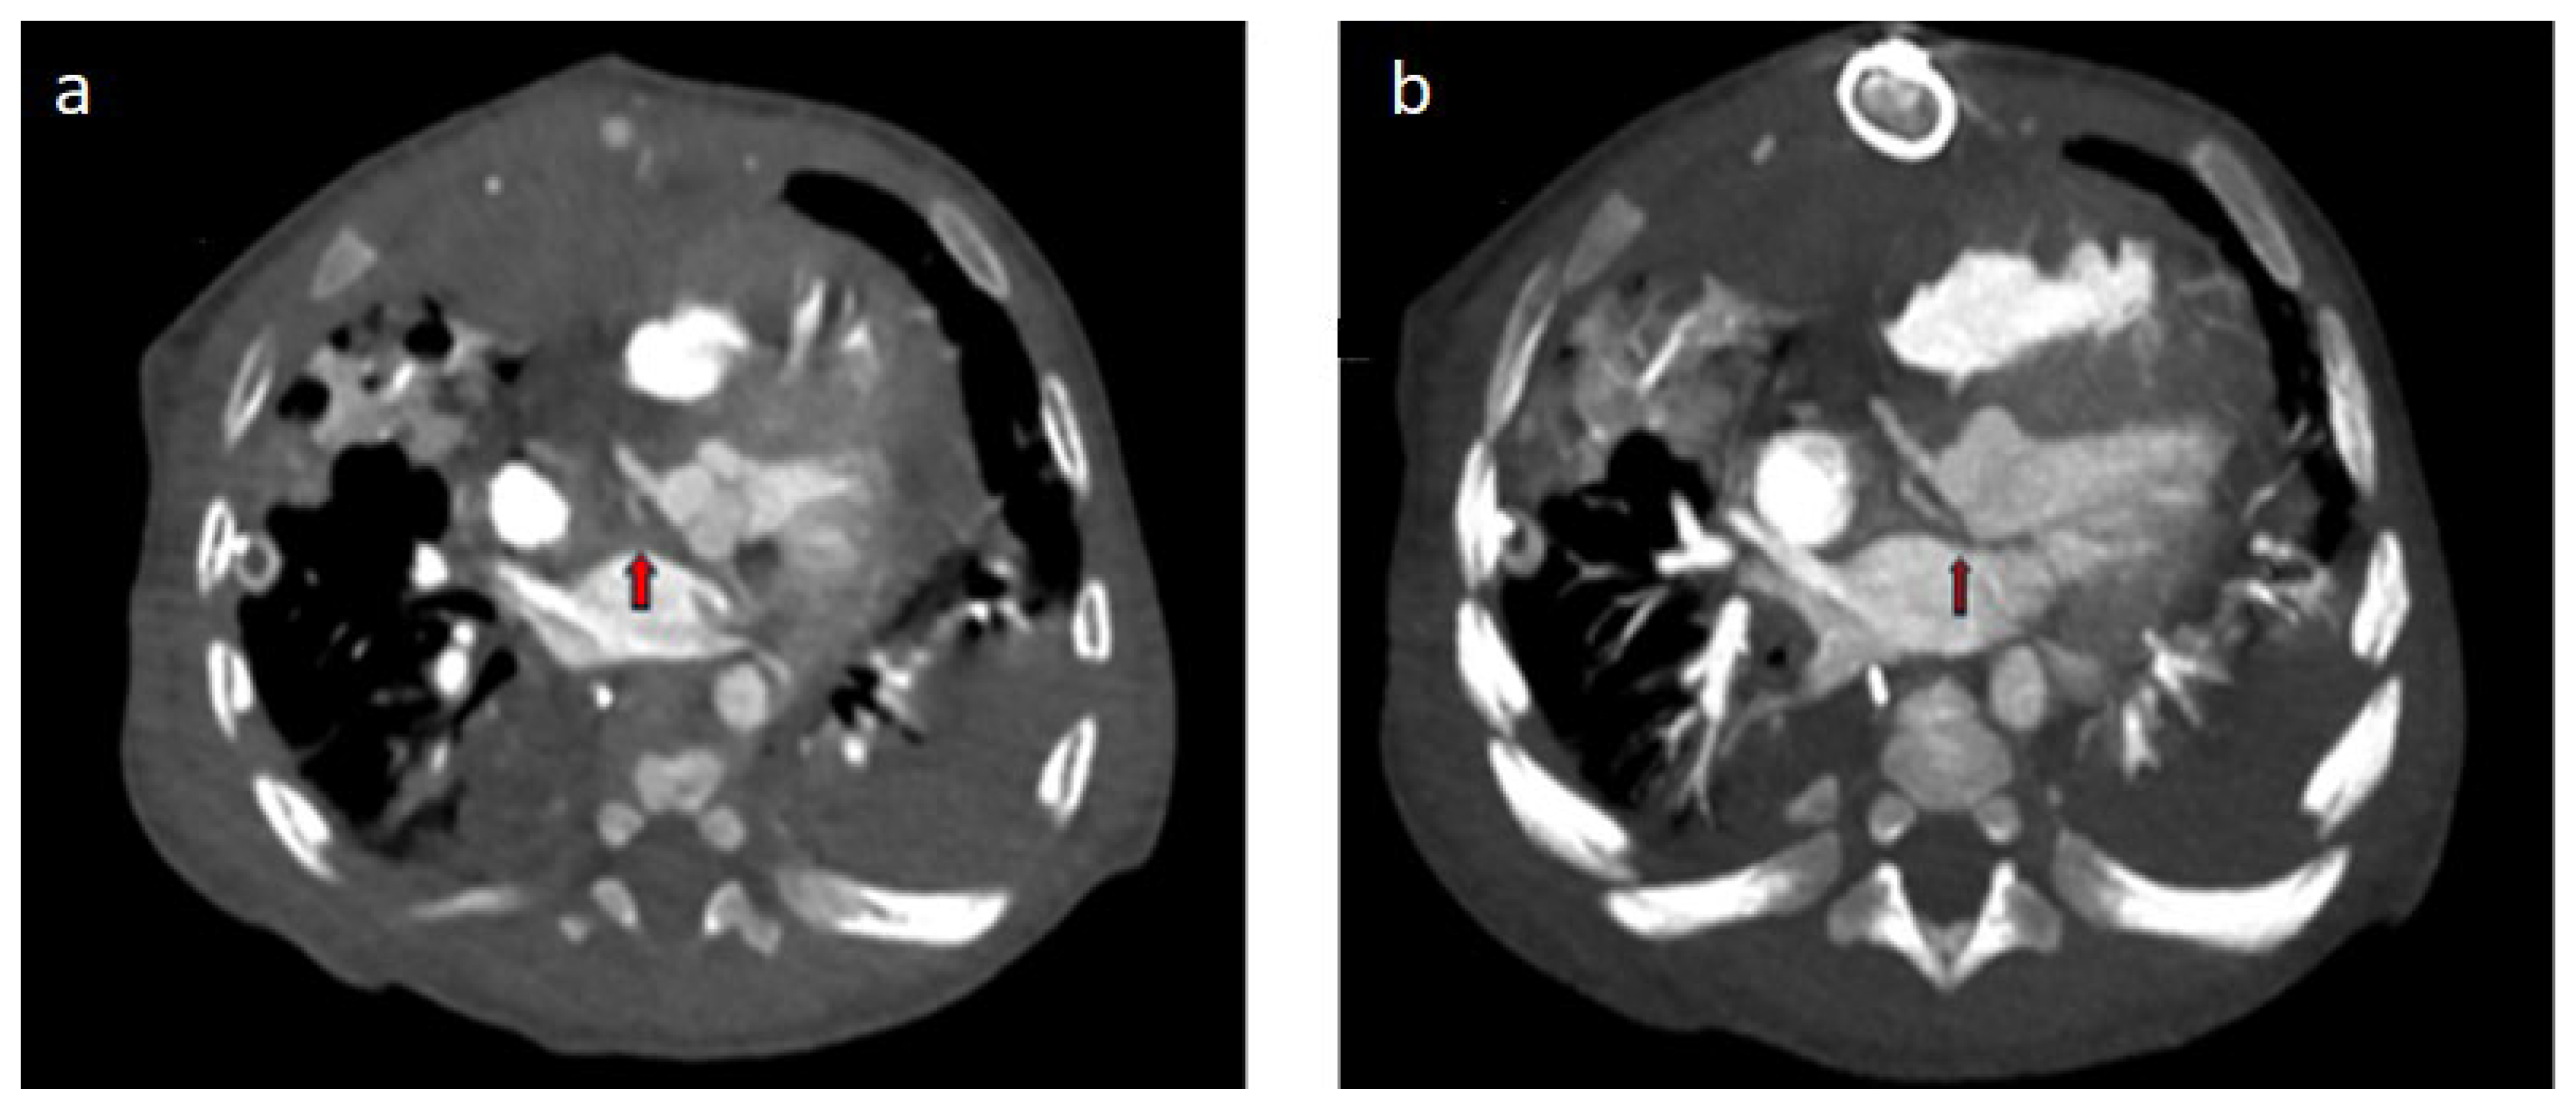

| Operated TGA (arterial switch) | Cx separated from the right coronary artery |

| Operated TGA (Rastelli) | Left coronary artery with interarterial course separated from the right coronary sinus |

| Single ventricle morphology (Fontan) | Cx leaving the right coronary sinus |

| Operated aortic stenosis, pulmonary stenosis (ROSS) | Left coronary artery leaving the right coronary sinus |